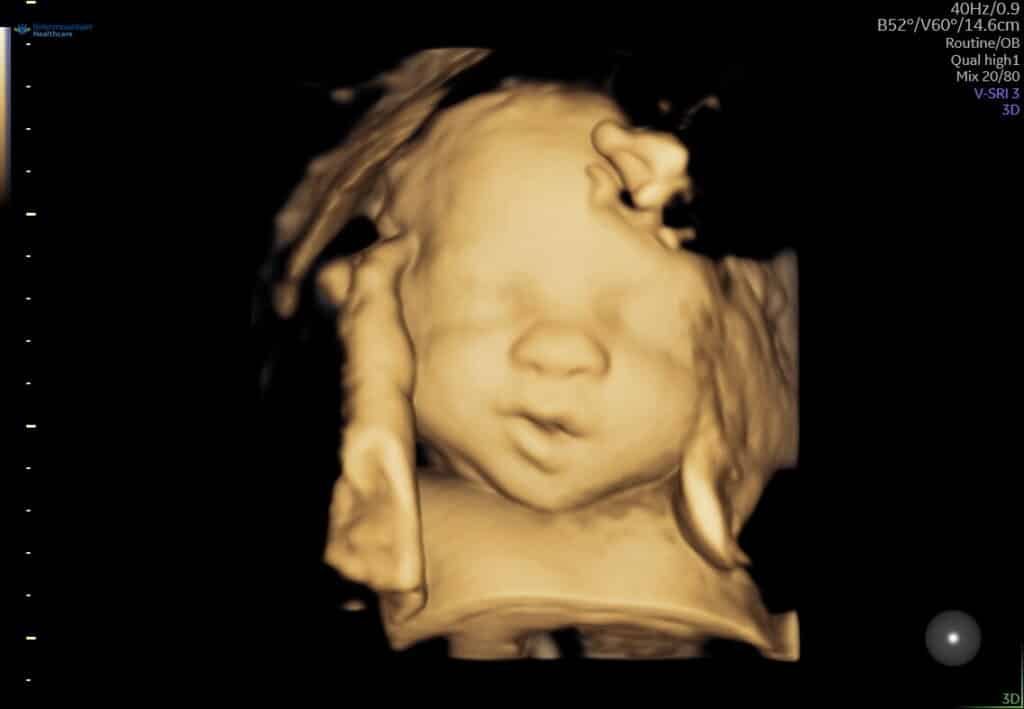

20 week ultrasound: We didn’t find out the gender of our baby. The baby measured big (90th percentile) and they casually asked me “Do you typically have 9 to 10 lb babies?”. What do you think we are having?

Since I am old, Maternal Fetal Medicine scheduled me for another ultrasound at 32 weeks. We found out that the baby still measuring at the 90th percentile but I also have a mild case of Polyhydramnios which means I have extra amniotic fluid. You should be at about 24 AFI and I have 26 AFI. There are different reasons why you may have extra amniotic fluid. They have ruled out all of those causes (swallowing difficulty, cleft lip, etc.) so they are just going to monitor it. The bummer thing is with the big baby and extra fluid it made me extra big (measuring 36 weeks along at 33 weeks). I think I look bigger (or as big) as I did when I was ready to deliver Madic and Emma. What do you think?